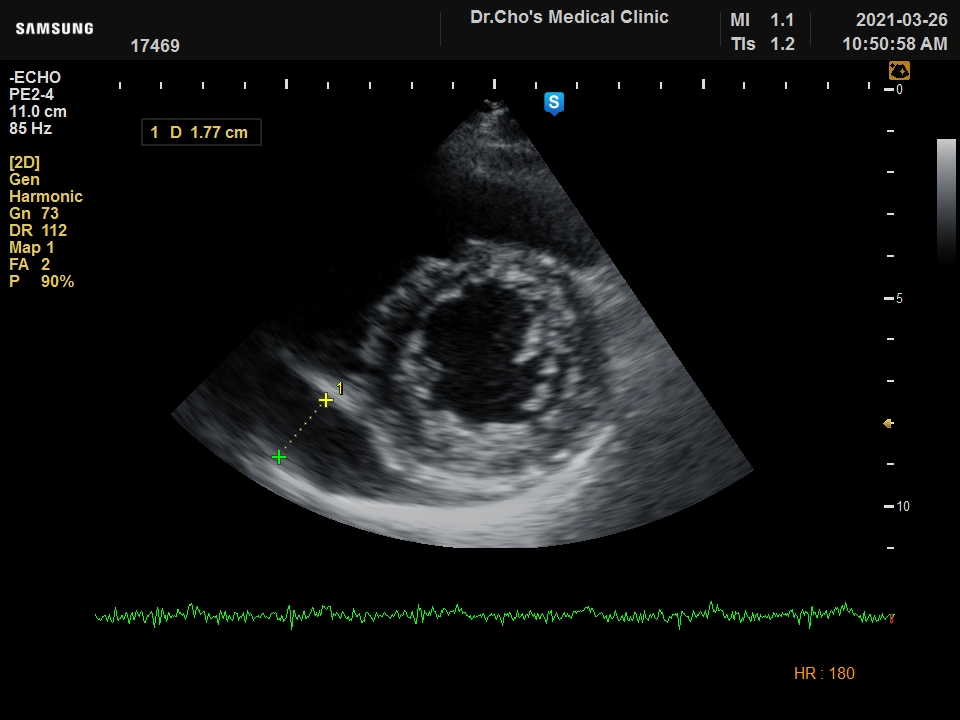

ÃÊÀ½ÆÄ°¶·¯¸®

¿ì½É½Ç °æ...